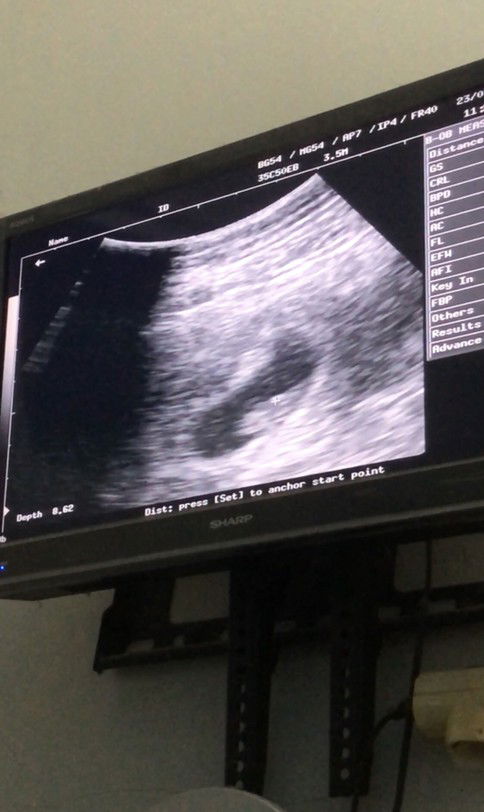

Hamil Uk 8w

alhamdulillah hasil usg tadi UK 8w janin ada dan sdh berdetak jantung😍 mudahan selalu sehat yaa . aamiin bunda bunda disini yg hamil 8w apa aja yg dirasain nih , sharing yuk klo sya skrg lgi sering pipis, trus tiap menjelang mlam sring demam dan mual tpi klo pagi siang aman aman aja😌

Alhamdulillah Bun. aku juga sudah USG usia kandungan 8w Alhamdulillah sudah ada janin nya dan terdengar detak jantung janin saat pemeriksaan USG